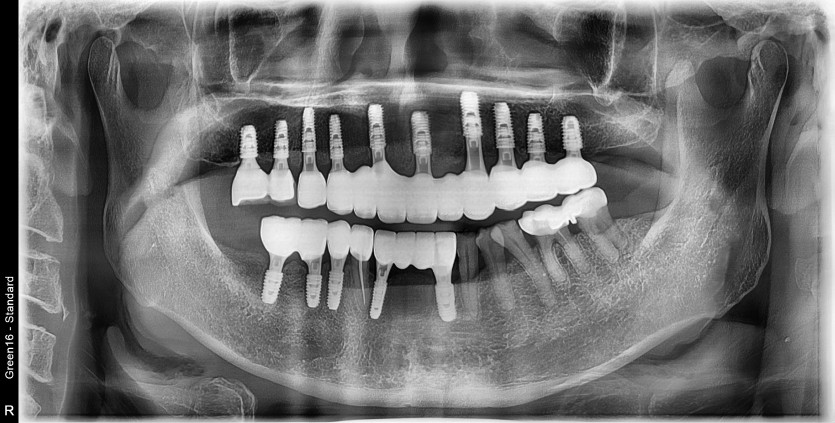

전체 임플란트 증례입니다.

15개의 임플란트로 완성하였습니다.